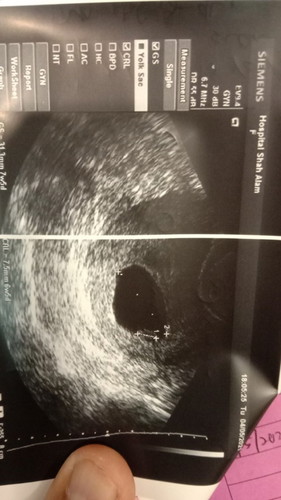

pengalaman sy keguguran kandungan 3bln...mase tu blm g scn kt klinik swsta...then sy pn x th yg kantung sy 0...bile keguguran tu then doc cek2 mmg hanya ade kantung sje..trpkse doc bg ubt thn sakit then x lame tu sy rase cm ade bende trkeluar dgn sndiri nye...bile sy g cek kt bilik air then pgl nurse...nurse cek mmg kantung sje yg keluar...bby xde pn...

Đọc thêmKalau boleh tggu je, jgn cuci dulu..tggu je selalunya dia akan keluar sendiri. Masa saya dulu pun sama, dia start with bleeding, then bbrpe hari lepas tu kantung tu keluar sendiri. Kalau tanda2 keguguran tu takde lagi..jaga je betul2 dulu sbb some cases sbnrnya tak kosong pun..(sbb nampak kantung puan mcm cantik je bulatnya)

Đọc thêmpada saya kalau boleh jangan cuci dulu. tunggu dia jatuh sendiri. sbb ada sy tgk beberapa cases sebenarnya kantung dia x kosong pun. cuma masa scan je x nampak. sbb kantung puan nampak bulat means nampak cantik. kalau mcm sy dulu gugur masa scan kantung saya dah x nampak bulat. nampak lonjong mcm dah tinggal nak turun je.

Saya pun mengalami macam sis . Dah 10 minggu tapi kantung saja nampak 🥺 risau sangat . Ini first baby saya

sama macam saya. bulan 3 aritu keguguran. kandungan 15minggu. tp nampak kantung shj😢